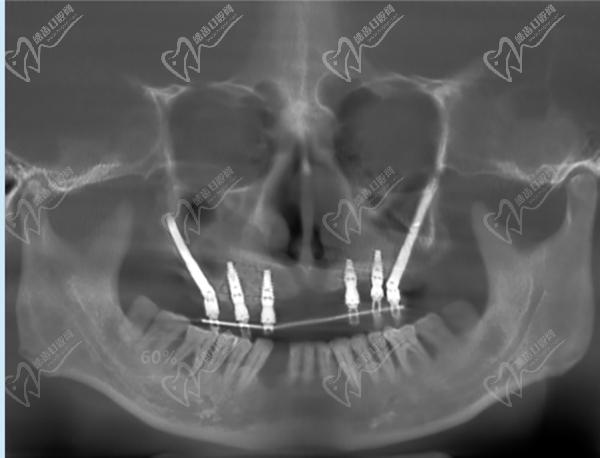

廣州柏德口腔主打德系口腔,引進(jìn)德國(guó)先 進(jìn)的口腔診療設(shè)備和技術(shù)。 注重?cái)?shù)字化技術(shù)應(yīng)用,提供更可靠的診療服務(wù)。 擁有一批經(jīng)驗(yàn)豐厚的醫(yī)生團(tuán)隊(duì),擅長(zhǎng)處理各種復(fù)雜的口腔問題。注重3D數(shù)字化種植技術(shù),術(shù)前種植牙方案模擬和設(shè)計(jì)更準(zhǔn)。也側(cè)重?cái)?shù)字化正畸技術(shù),矯正過程更精 準(zhǔn)高 效。